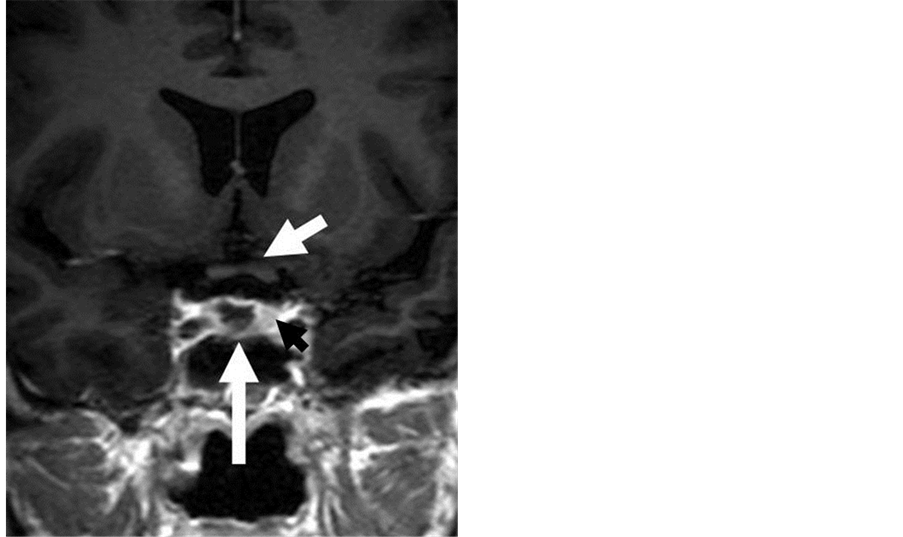

A total of 106 patients (64 female, 42 male) affected by secreting microadenomas were considered. Patients age was between 22 and 62 years (average 47.4). Patients affected by microadenoma invading cavernous sinus were not considered in the study, because our therapeutic strategy in these cases is represented by surgery for the intrasellar part of the adenoma and postoperative stereotactic radiotherapy for the intracavernous part of tumour. All were operated through transsphenoidal surgery from 1998 through to 2008; in 54 (group 1) intraoperative absolute alcohol was applied, while in the other 52 (group 2) it was not employed (Table 1). Preoperative diagnosis was assessed by hormonal studies which revealed hormonal hypersecretion, by clinical signs and symptoms related to hormonal hypersecretion, and by 1.5 tesla MRI which showed in all cases a clear microadenoma and also a delay of enhancement, at the dynamic sequence, of a portion less than 10 mm into the context of the pituitary gland (Figure 1); pituitary stalk deviation was present in 79% of microadenomas. Postoperative controls were assessed by 1.5 tesla MRI performed after 6 months and then once at year for 5 years, and by hormonal exams performed in the immediate postoperative period (5 - 10 days), after three, six months and afterwards once at year. In our opinion and experience, postoperative MRI after transsphenoidal surgery for microadenomas plays a minor role than postoperative blood hormone levels to evaluate the results; so that postoperative evaluations and indications were mainly performed on the basis of blood hormone levels. Magnetic resonance image was important in patients with postoperative hormonal persistence or hormonal recurrence who were submitted to stereotactic radiotherapy.

Figure 1. Post-contrast T1 coronal MR image showing a microadenoma in the median portion and in the right side of the pituitary gland. Long white arrow: microadenoma. Short white arrow: optic chiasm. Black arrow: left portion of pituitary gland.